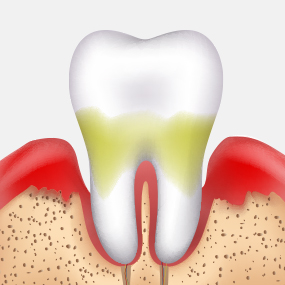

충치는 스스로 회복되지 않기 때문에,

정기적인 검진과 조기 치료가 건강한 치아를 오래 보존하는 가장 좋은 방법입니다.